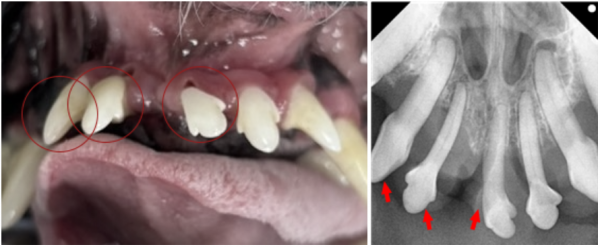

반면 좌측 어금니는 상황이 다르게 나타났습니다.

207번 치아 distal root와

208번 치아 mesial root 부위에서

치조골 소실은 있었으나,

· 치조골 손실 50% 미만

· 치아 유동성 없음

· furcation involvement 없음

즉, 강아지 치아를 살릴 수 있는 조건이었고,

보호자님과 상의 후 발치 대신 GBR/GTR 보존치료로 결정했습니다.